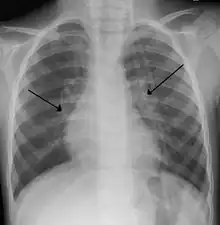

Chest X-rays findings in children with RSV bronchiolitis are generally nonspecific and include perihilar markings, patchy hyperinflation, and atelectasis.[16] However, the American Academy of Pediatrics (AAP) does not recommend routine imaging for children with presumed RSV bronchiolitis because it does not change clinical outcomes and is associated with increased antibiotic use.[16][5] Chest X-ray is sometimes considered when the diagnosis of bronchiolitis is unclear or when there is an unexpected worsening.[5] In adults with RSV infection, chest films are often normal or demonstrate nonspecific changes consistent with viral pneumonia, such as patchy bilateral infiltrates.[36]